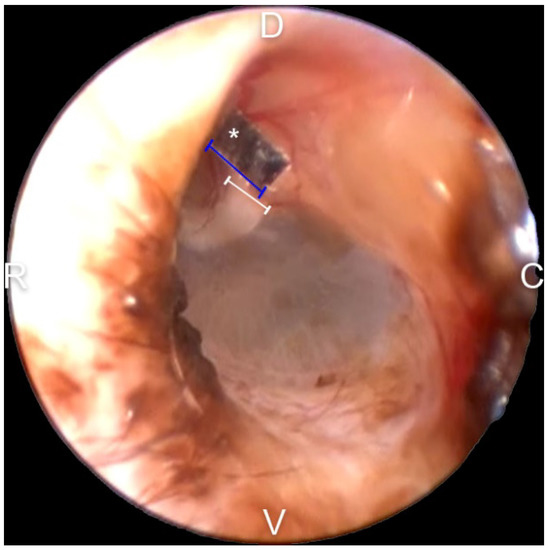

2.7. Malleus Width Measurement for Calibration

2.8. Evaluation of the TM EM Rate

3.2. Malleus Width Measurement and Calibration